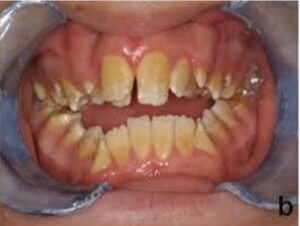

Sistemik faktörlerin sebep olduğu renklenmeler şunlardır: Okronozis, amelogenezis imperfekta, dentinogenesis imperfekta, fenilketonüri, konjenital hiperbilurubinemi, konjenital eritropoetik porfiria, dentinal displazi, tetrasiklin renklenmesi ve florozis.

Şekil 1 Amelogenezis imperfekta

Şekil 2 Dentinogenezis imperfekta